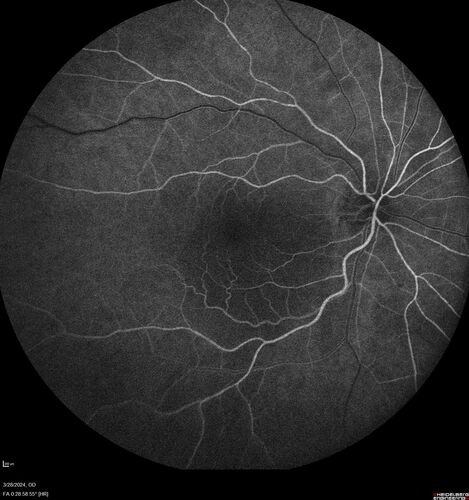

Serous Macular Detachment from Small Choroidal Melanoma

72 year old female misdiagnosed as CSR who had small choroidal melanoms.